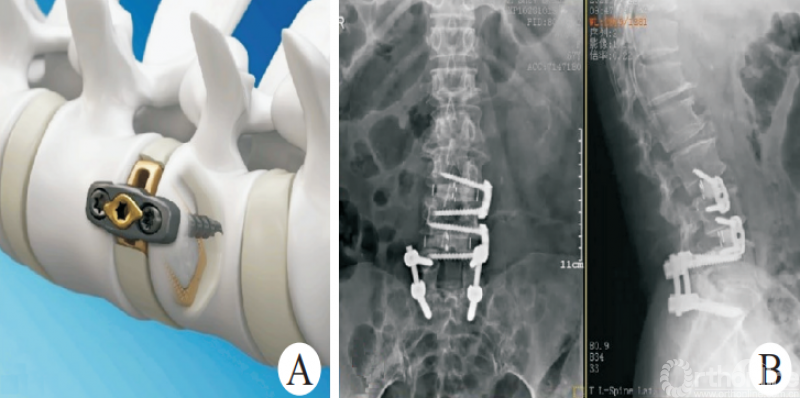

3.2 Stand⁃alone OLIF

尽管经典的OLIF手术能够有效解决众多腰椎失稳性疾病,但是术中变换体位、二期手术等因素限制了其应用。Stand-alone OLIF(图5)的概念也应运而生,Stand-alone OLIF能够避免椎旁肌肉等软组织的损伤,对于改善术后因肌肉剥离等引起的腰背部疼痛有一定的意义。

图5 Stand-alone OLIF

生物力学试验证明,侧方融合器可以有效重建脊柱的稳定性,也为Stand-Alone OLIF提供了理论依据[30-31]。ZHU等[32]通过比较Stand ⁃alone OLIF与PLIF两种手术方式治疗邻椎病,发现OLIF组术中出血量少,手术时间短,卧床休息时间短,住院时间短,且都能获得满意的融合效果。

UDBY等[33]回顾性研究对比Stand-alone前路融合与联合后路钉棒固定两种手术方式,结果发现,Stand-alone技术在ODI、VAS、手术时间、失血量和患者满意度等方面有显著优势。MANZUR等[34]回顾性分析了Stand-alone前路融合的融合率为88.6%,总体上获得了较高的融合率。因此,Stand-alone OLIF是一种有效的椎体间融合术式,且具有手术时间短、出血量少、患者满意度高、术后疼痛轻等优势。对于合适的患者选择Stand-alone OLIF,既能获得满意的疗效,又能尽可能减小损伤。

但是Stand-alone OLIF有其应用边界。对于骨密度降低[35]、术中终板损伤,术中前纵韧带损伤、冠状面失衡(C7铅垂线距离骶骨正中线>2cm)、动力位X线片显示动态不稳(过伸过屈位节段位移>3mm或角度变化>11°)、Ⅱ度退行性滑移、矢状面失衡(C7铅垂线距离骶骨后上角>2.5cm)、峡部裂滑移、邻椎病发生在原有融合节段远端、融合节段≥3个、Ⅱ~Ⅲ度关节突关节骨关节炎(关节突关节间隙狭窄,伴关节突明显增生肥大、硬化、骨赘增生、关节面破坏)等患者,建议联合内固定,以增强稳定性、降低翻修等的风险。